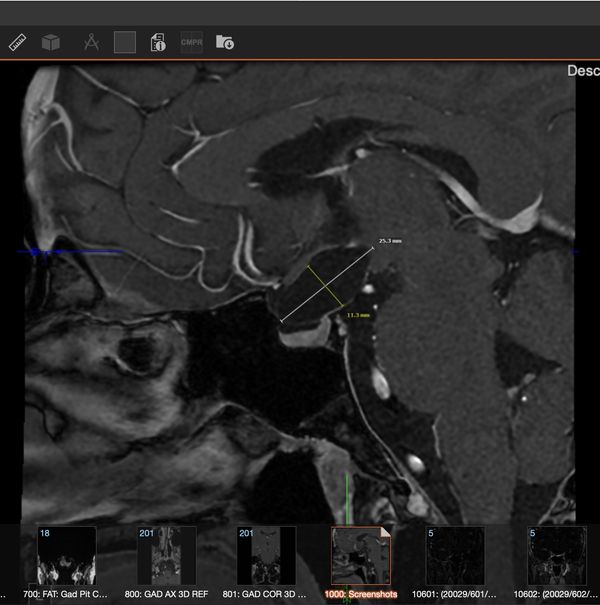

THEY SAID IT’S SHRINKING! THE CHEMO IS WORKING! I am still waiting on my official radiology report but my neuro oncologist measured it on my MRI and he thinks it shrunk 30%. What’s messed up is my mind and body…

Okay, first off, I had my two month MRI yesterday and learned that the tumor shrunk another 30-40% !! Modern medicine, especially precision oncology, is f****** AMAZING. It's crazy to think that exactly two years ago I was being wheeled…